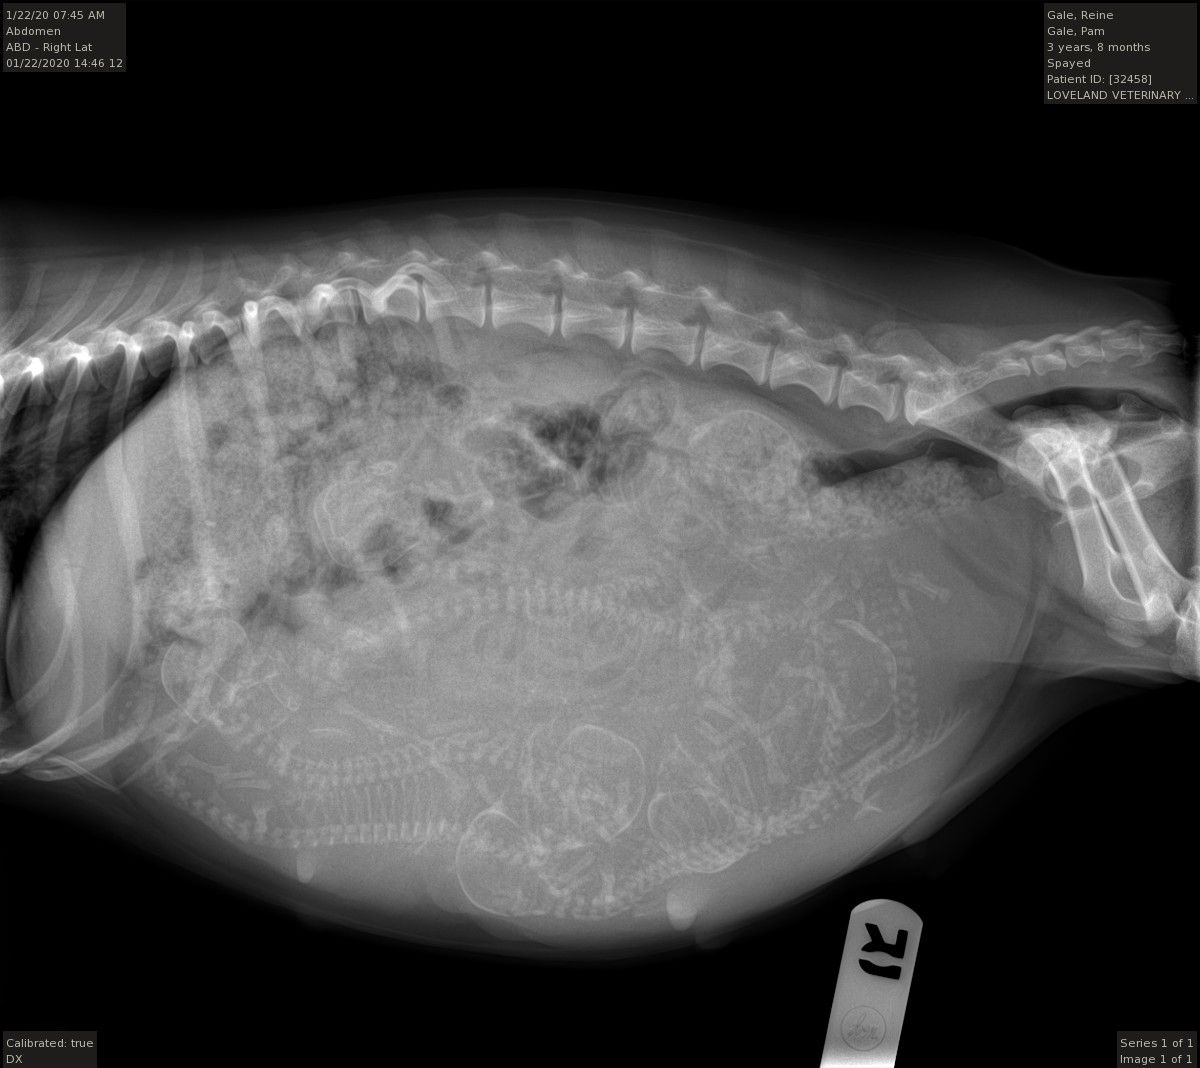

1/20/2020 - Xrayed Reine - she has SEVEN puppies in there!!! Holy cow - that is my biggest litter yet.

1/28/2020 - Babies are here!!! We have 6 girls and 1 boy. We decided to do a c-section as she was so big I was afraid she might get in to trouble. So, I opted to do a planned c-section. All 7 babies are great - scroll down for some pictures and puppy breath!